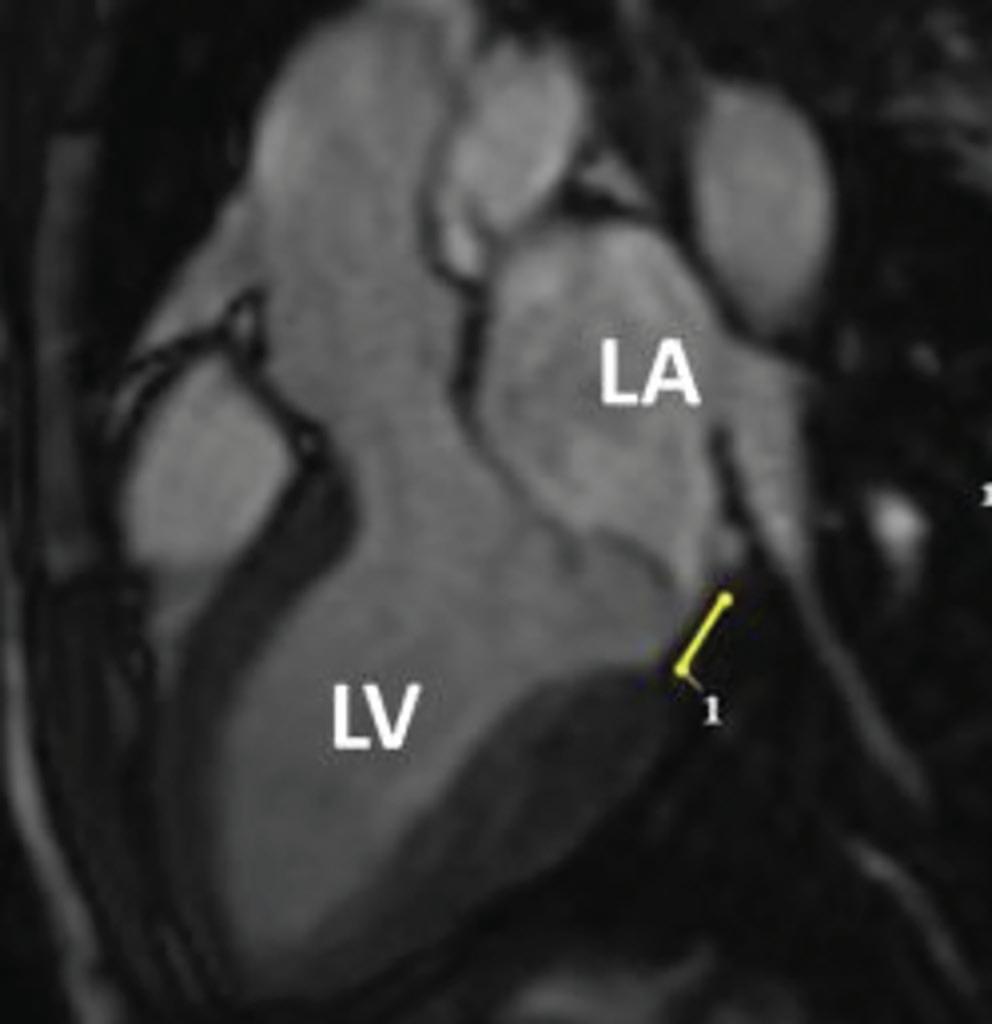

Figure 6: Ventricular Ablation Lesion Assessment

Preprocedural LGE-MRI (1 day before VT ablation)

Ablation points

Post-ablation LGE-MRI (3 months after VT ablation)

Left: 3D reconstruction of the left ventricle with LGE-based colour-coding based on thresholds for dense scar (red, >60% maximum of signal intensity) and border zone (yellow, 40–60% of maximum signal intensity), mapped using ADAS 3D. Shown are the layers at 30% of the transmurality (from endocardial to epicardial). For the post-ablation LGE-MRI (lower panel), an additional 3D reconstruction of the manually defined dark core in red (black arrow) is depicted. Blue lines indicate the plane of the short-axis slices on the right. The ablation points (TactiCath, Abbott Medical) are visualised using a 3D mapping system (EnSite Precision, Abbott Medical). Middle: Overlay of the T1-weighted short-axis slices with the colour-coding described above. The central hypoenhancement dark core of the ablation lesion is manually delineated (red border) to avoid misinterpretation as healthy tissue. Right: T1-weighted short-axis LGE-MRI slices without colour-coding. LGE = late gadolinium enhancement; VT = ventricular tachycardia.